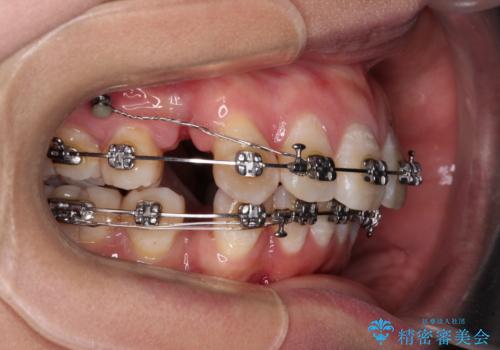

- メタルブラケット

骨格的に上顎歯列が前方位にあり、口元の突出感が顕著な状態で、上下左右の第一小臼歯4本を抜歯して、ワイヤー装置での抜歯矯正を行うこととしました。

奥歯の咬み合わせ改善のために、アンカースクリューの使用と上顎左右第一小臼歯の抜歯のタイミングをコントロールして、理想的な咬み合わせに仕上げていくこととしました。